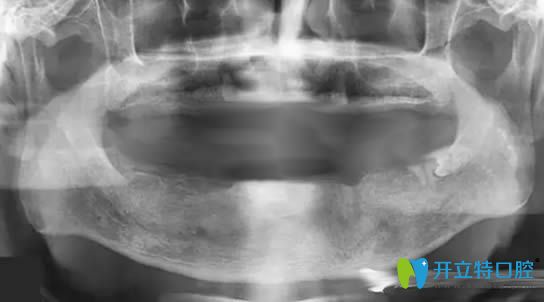

帶10年活動(dòng)假牙萎縮的牙槽骨圖片

但好景卻不長(zhǎng),在2025年的時(shí)候,總出現(xiàn)黏膜潰瘍等牙周病,我讓反復(fù)的到口腔進(jìn)行治療......讓我的飲食成了的問(wèn)題。為了改善現(xiàn)狀,孩子帶我去了一家私人牙科進(jìn)行咨詢,說(shuō)我佩戴活動(dòng)假牙時(shí)間長(zhǎng)了,造成了牙槽骨低平,無(wú)法讓活動(dòng)義齒取得好的固位,并且,就連做種植牙的基礎(chǔ)條件都沒(méi)有了......

牙槽骨萎縮全景片